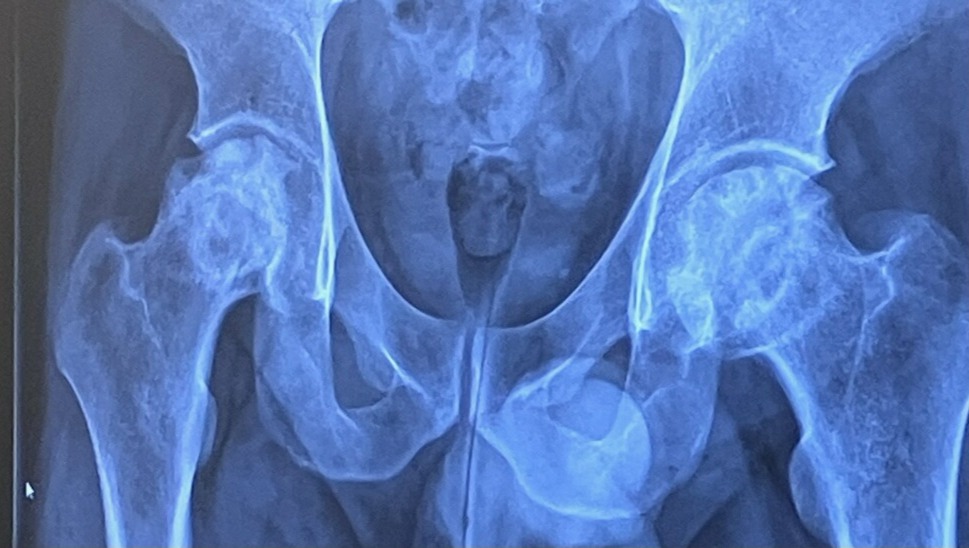

We come to you with a heartfelt plea to support our dear friends, Andy and Alle Jacobsen, who are facing an incredibly tough situation. Andy has been diagnosed with avascular necrosis (AVN), a debilitating condition that has severely impacted his hip joints. This condition has caused immense pain as his joints collapsed and now bone spurs stab into the joint. This has obviously limited his mobility, leading to the heartbreaking loss of his job.

Image of Andy's hips